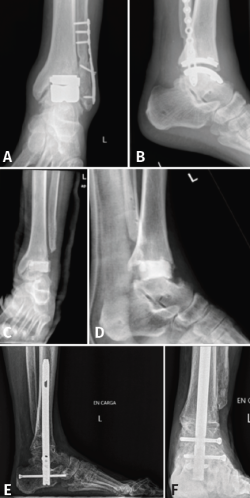

Figura 5. Radiografías del caso 2. Hombre de 55 años con artrodesis tras rescate de prótesis de tobillo. A y B: radiografías anteroposterior y lateral 1 año tras la prótesis de tobillo de tipo TM sin signos de aflojamiento ni movilización del material; C y D: radiografías anteroposterior y lateral posquirúrgicas tras el primer tiempo de retirada de la prótesis y espaciador de cemento; E y F: radiografías anteroposterior y lateral 10 meses tras la artrodesis tibiocalcánea en las que se observa consolidación de las interfases tibia-aloinjerto y astrágalo-aloinjerto.

Un varón de 55 años es intervenido en 2020 por artrosis postraumática tibiotalar mediante prótesis total de tobillo de metal trabecular. La evolución del paciente es satisfactoria, pero tras un año de la cirugía presenta dolor progresivo que le dificulta la marcha. Se realiza radiografía anteroposterior y lateral sin signos de aflojamiento ni movilización de los componentes (Figura 5). Ante la sospecha de una posible infección se realiza analítica con reactantes de fase aguda con valores dentro de la normalidad y gammagrafía con leucocitos marcados que informa de captación en fase inflamatoria a nivel del maléolo interno.

Ante estos resultados y por la posible infección de la prótesis, se decide realizar EMO de la placa del peroné y toma de cultivos, que son positivos para Staphylococcus epidermidis meticilín resistente. Antes de realizar la cirugía, un año y medio tras la implantación de la prótesis, el paciente acude a urgencias por la aparición de una fístula con salida de material purulento en la zona medial. Por este motivo, se realiza tratamiento antibiótico con linezolid y rifampicina, y se propone al paciente artrodesis TTC de rescate en 2 tiempos: un primer tiempo de retirada de la prótesis, exéresis del peroné distal para preparar la zona para la cirugía posterior, toma de muestras para cultivo y espaciador con cemento con antibiótico (vancomicina y gentamicina) (Figura 5). El cultivo de la muestra intraquirúrgica fue positivo para Staphylococcus lugdunensis sensible a linezolid, siendo necesario asociar dicho antibiótico durante 2 meses.

Finalmente, 4 meses tras la retirada de la prótesis y comprobando que los parámetros clínicos y analíticos estaban normalizados, se realiza el segundo tiempo, procediéndose a artrodesis TTC con aloinjerto estructural debido al poco stock óseo remanente en el astrágalo. Un año tras la cirugía, el paciente se encuentra asintomático, presenta apoyo plantígrado y una escala de la AOFAS de 67. Los parámetros inflamatorios analíticos se han normalizado y en la TC de control se observa consolidación > 90% de las interfases injerto-tibia e injerto-astrágalo, aunque también pseudoartrosis de la articulación subtalar (Figura 4). De nuevo, se realizan las medias de altura del injerto, siendo en la radiografía posquirúrgica inmediata de 12 mm y 1 año tras la cirugía de 9,03 mm.